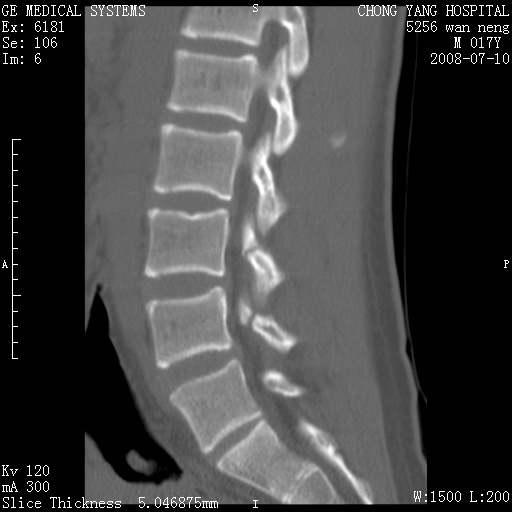

重建图像见多个椎弓峡部不连(不足为据),平扫未见异常。

腰3、4椎弓崩裂

腰3、4椎弓不连

支持:腰3、4椎弓峡部崩裂。

腰3、4椎弓峡部不连

支持:腰3、4椎弓峡部崩解。

图片漂亮,目前也只能看到腰3、4骨质不连

腰3、4椎弓峡部裂。

腰3、4椎弓峡部裂。支持

支持腰3、4椎弓峡部崩裂。